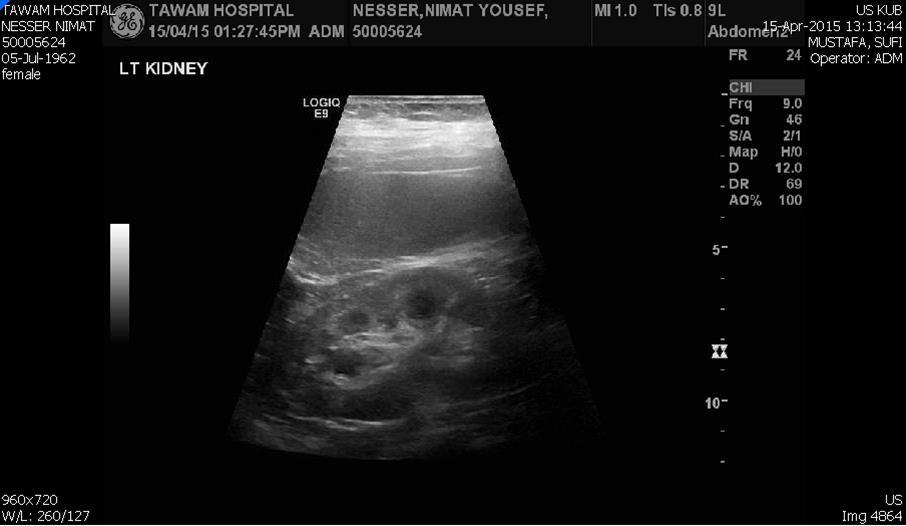

Blood tests on April 14th showed: Na = 131, K = 5.1, Urea = 6.9, S. Creatinine = 96, and eGFR = 61ml/min. Urine analysis and cultures confirmed E. coli urosepsis, blood cultures were negative. Renal US revealed echogenic kidneys, mild bilateral hydronephrosis of about 12 mm with normal ureters and urinary bladder (Figure 1 and Figure 2). Treatment with oral antibiotics resulted in improvement of temperature and dysuria. On April 20th patient seen by endocrinology and nephrology because of persistent back pain, dapagliflozin was discontinued and followed by resolution of symptoms in few days. Patient had two kidney ultrasounds in May and June, both indicated gradual resolution of bilateral hydronephrosis. Repeat CT of the abdomen on July 7th revealed complete resolution of hydronephrosis (Figure 3). Most recent eGFR is 72 ml/min.

Figure 2.Left kidney hydronephrosis